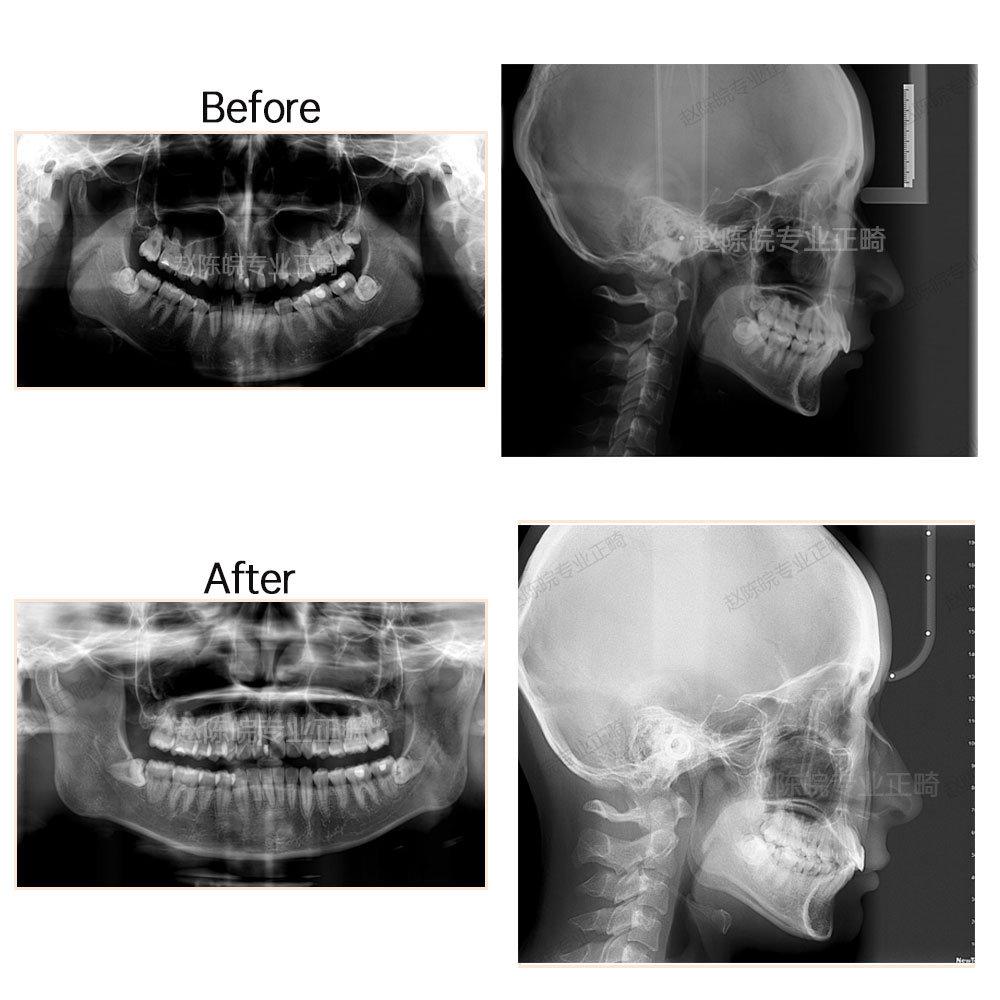

?矯正前后X線片前后對(duì)比圖(觀察對(duì)比側(cè)面顱骨情況及牙體牙周情況)

測(cè)量分析模型分析:上頜擁擠度3.5mm,下頜擁擠度3.5mm,前牙bolton比81.6%,spee曲線3.8mm

7.骨性2類(lèi),下頜骨發(fā)育稍不足。

診斷:安氏2類(lèi),骨性2類(lèi)錯(cuò)頜

上頜推磨牙向后加適量片切,內(nèi)收前牙,糾正上中線;下頜擴(kuò)弓加前牙適量片切排齊牙列,壓低下前牙整平spee曲線。

完成結(jié)果:達(dá)到矯治目標(biāo),牙列排齊,中線就真正,咬合中性,覆合覆蓋正常。